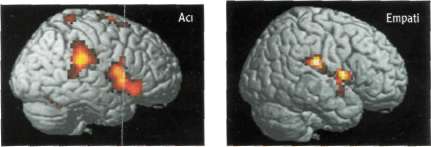

Beyin Sevilenin Acısını da Duyuyor

Sinirbilim (nöroloji) araştırmacıları beyin görüntüleme teknikleri kullanarak insanın beyninin, sevdiği yakınlarının acılarını da kısman hissettiğini belirlediler. İnsanın başkalarının hissettiklerini hissedebilme yeteneği (empati), insanların sosyal çevrelerine uyum sağlamalarında büyük önem taşıyan kişisel ilişkiler geliştirmelerinde yardımcı oluyor. Londra'daki University College araştırmacılarından Tania Singer yönetimindeki ekip, aralannda romantik ilişkiler bulunan 16 çiftle deneyler yürütmüş. Deneylerde odaya adılan çiftlerden kadın bir manyetik rezonans görüntüleme makinesi içine alınıyor ve ya kendi eline ya da partnerinin eline bir saniye süreyle bir elektrik şoku uygulanırken beyninin görüntüleri izleniyor. Kadın, erkeği göremiyor; ancak, bir ekrandan şokun kendisine mi, yoksa partnerine mi uygulanacağını ve derecesini görebiliyor.

|

Kadına şiddetli bir şok uygulandığında beyninin duygularla ilgili limbik bölgesinde acı bölgesi hareketleniyor. Bunlar, ön singulat korteksi, beyin kabuğundan (korteks) alınan bilgileri ileten insula, tüm duyulann kortekse gitmeden önce uğradığı röle istasyonu görevi yapan talamus ve dokunma, ağrı ısı gibi duyulan algılayan duyu korteksi (somatosensory korteks) gibi bölgelerden oluşuyor. Ancak kadının, partnerine şiddetli bir şok uygulanacağını öğrenince empati nedeniyle harekete geçen beyin bölgeleri arasında, kendi bedenine ait acı vb gibi duyulan algılayan duyu korteksi bulunmuyor. Ancak, duyulan değil de zihinde canlandınlan acıyla ilgili bölgeler hem kişisel acı duyumunda, hem de partnere uygulanan acı sırasında harekete geçiyor. Bu da Singer'e göre empatinin temelini oluşturuyor. Araştırmacıların deneylerden elde ettikleri bir başka sonuç da, empati nedeniyle harekete geçen aynı nöron gruplannın, kişinin kendine bir acı uygulanacağı beklentisi karşısında da harekete geçmesi.

Scrace, 20 Şubat 2004